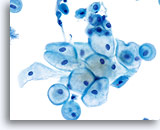

Benign Appearing Endometrial Cells

Endometrial cells may display a wide range of nuclear and cytoplasmic size, as well as architectural configuration. Endometrial cell groups tend to round up in ThinPrep solution. The nuclei are well preserved and appear crisp with distinct, active chromatin; chromocenters are frequently noted.

Bethesda 2014 recommends the reporting of benign appearing exfoliated endometrial cells in women age 45 and above, regardless of clinical history. The general categorization “Other” was included in the Bethesda 2001 lexicon for this purpose. Histiocytes, stromal cells and abraded endometrial cells do not have the same significance as exfoliated endometrial cells and should not be considered in the same context. While most often benign, identification of endometrial cells, particularly if not associated with menses or after menopause, may indicate risk for an endometrial abnormality.